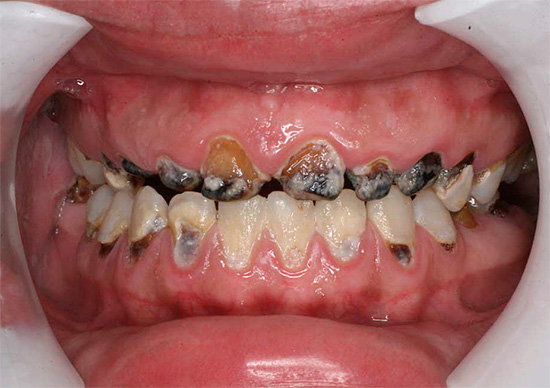

E questa foto mostra un altro esempio di come i denti sono stati colpiti carie generalizzata. Questa è una forma molto pericolosa della malattia, che minaccia una persona con la perdita di una parte significativa dei denti, la depulpazione (rimozione dei nervi) e l'installazione di corone:

Nell'aspetto e nella natura del corso, la carie delle bottiglie è quasi generalizzata. La principale differenza tra queste malattie è l'età delle persone che colpiscono: la carie in bottiglia si sviluppa principalmente nei bambini da 1 a 3 anni. Questo è spesso associato a un'immunità indebolita e malattie somatiche in tenera età.

Immagini della bottiglia della carie: